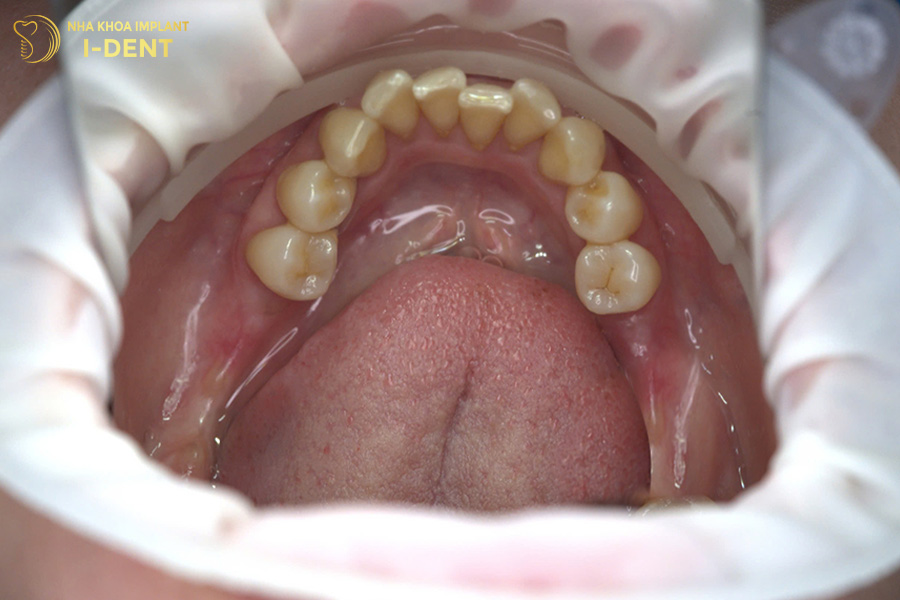

Tình trạng răng ban đầu của cô Kim Liên

Sau thăm khám, bác sĩ Đình Tín đã chỉ định cho cô phương pháp cấy ghép Implant All-on-4, sử dụng dòng trụ implant Straumann SLActive của Thụy Sĩ để giúp cô khôi phục lại toàn bộ răng mất ở hàm trên.

Sau điều trị, cô Kim Liên đã lấy lại khả năng ăn nhai cứng chắc, cùng với đó là răng sứ được phục hình có màu sắc tự nhiên, hài hòa với tổng thể khuôn mặt.

Tình trạng răng sau khi cấy ghép Implant của cô Kim Liên